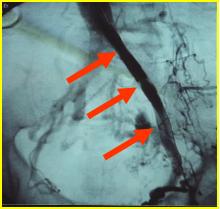

急诊造影:股总静脉、髂内外静脉大量新鲜血栓形成,见图4

图4